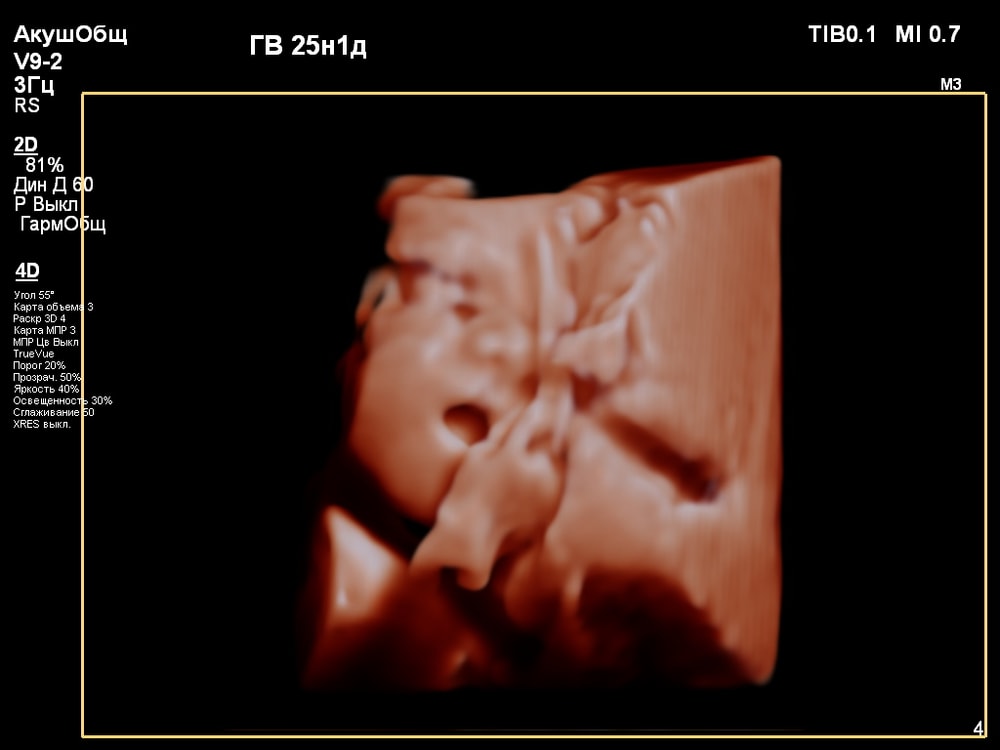

3D/4D УЗИ в 25 недель

УЗИ, КТГ, доплерПервая фотосессия малыша ещё в животике!😍 СНИМКИ С УЗИ👇

Когда переключили на 4D режим было сначала непонятно, что изображено на экране. Но врач всё показывала и обьясняла что на нём: где носик, губки, подбородок, что у личика ручки, малыш что-то жуёт, губками шевелит. Тогда картина начала вырисовываться и всё стало понятно, и в движении тоже)).

За 30 мин удалось увидеть многое (ребёночек не спал)! Он у меня в принципе парень активный, особенно лёжа на спине): на УЗИ, ещё в самом начале, малыш показал указательный палец и почесал им нос 😂, потом пытался большой палец засунуть в рот и пососать. Забавно было, когда он начал зевать и прикрывать ротик ладонью (воспитанный растёт). Ну и конечно, на радость родителям малыш улыбался🥰. Александра Евгеньевна смогла поймать все эти моменты и запечатлеть на снимке). Когда ребёночек закрывался, отворачивался - врач проводила общее 2D исследование, потом возвращалась к 4D.

😁😍🥹Я ИСПЫТАЛА НЕВЕРОЯТНУЮ РАДОСТЬ, ВОСТОРГ И УМИЛЕНИЕ)): впервые увидеть не абстрактные черно-белые тени, а узнаваемое личико своего ребенка, его движения – это мощнейший эмоциональный опыт, укрепляющий связь с малышом еще до рождения! Увидеть, как малыш активно двигается, зевает, сосет пальчик, улыбается – вызывает бурю положительных эмоций.

Иногда получить хорошую картинку сложно. Качество изображения сильно зависит от положения плода, количества околоплодных вод, расположения плаценты, толщины брюшной стенки. Мне в этом плане повезло, плацента была расположена по задней стенке матки, брюшная стенка у меня тоненькая, околоплодные воды в норме, малыш был в движении и можно было разглядеть его профиль.